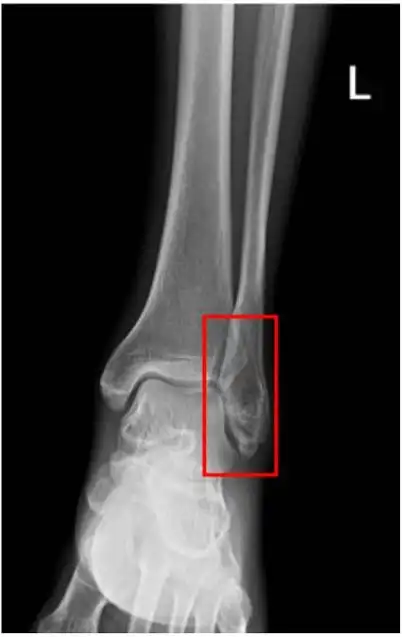

【读片】左踝.x [病例帖]